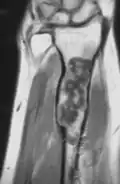

MRI showing enchondromas localized in the lower part of the radius of a 37-year-old patient affected with Ollier disease -

MRI showing enchondromas localized in the lower part of the radius of a 37-year-old patient affected with Ollier disease. -

Magnetic resonance imaging (MRI), ultrasound, and scintigraphy are generally not practical for diagnostic purposes. X-rays are not as effective in the monitoring or evaluation of enchondromas due to frequent localized changes also sometimes due to the large number of enchondromas. MRI can sometimes however be used to monitor and evaluate symptomatic lesions in the case of potential malignant transformations.